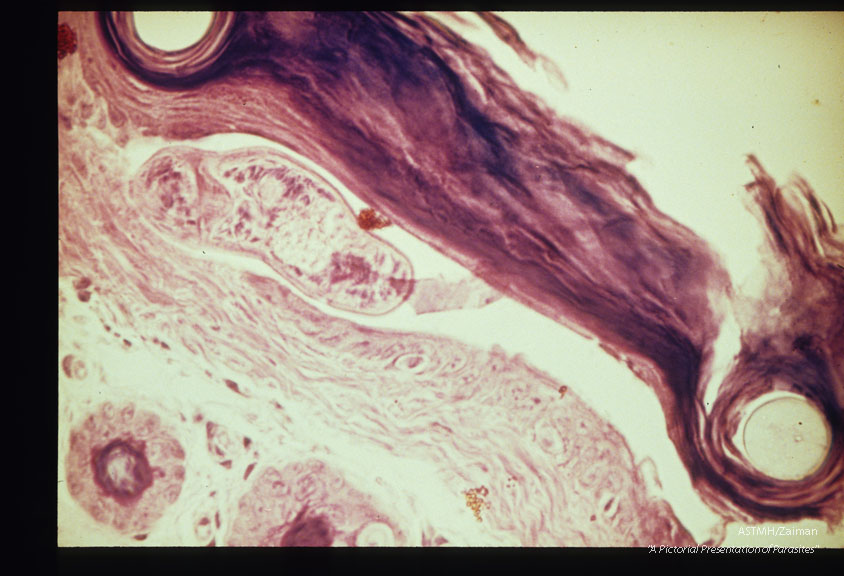

Cercariae before and after skin penetration. These slides compliment slides 1258 through 1262.

Schistosoma

Description: Cercariae before and after skin penetration. These slides compliment slides 1258 through 1262.